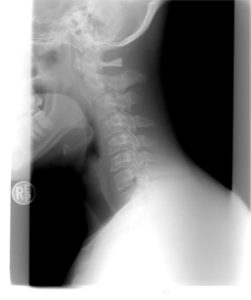

Utrpěli jste poranění krční páteře při autonehodě, kterou jste nezavinili a řešíte získání odškodnění? Poradíme rychle v tomto článku.

Poranění krční páteře je častým zraněním při dopravní nehodě. Toto zranění se však nemusí projevit ihned po dopravní nehodě, ale bolesti krční páteře mohou nastat až několik dnů po autonehodě. Z naší právní praxe odškodnění dopravních nehod doporučujeme neprodleně navštívit lékaře, jakmile se projeví bolest páteře. Lékařské zprávy budou velmi důležité pro následné uplatnění a získání odškodnění za opěrkový syndrom/whiplash.

Poranění krční páteře při autonehodě může způsobit pracovní neschopnost, potřebu návštěv řady lékařů a bohužel také vznik trvalých následků. Obecně lze tak okruh náhrad odškodnění pro opěrkový syndrom stanovit na:

Whiplash syndrom tak nemusí představovat pouze marginální zdravotní obtíže, ale také potřebu kontinuální léčby a odborných vyšetření. Každý případ je nutné posoudit individuálně ke stanovení, které náhrady lze žádat k odškodnění